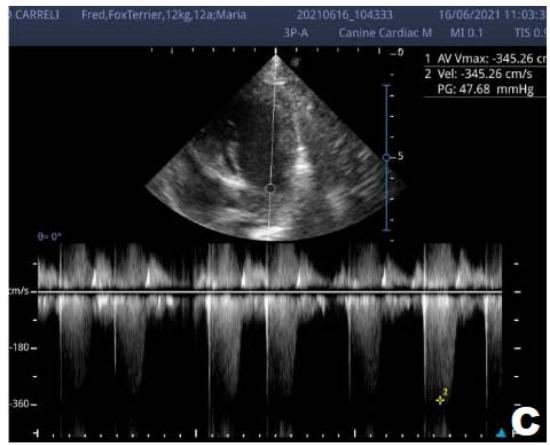

An echocardiogram (ECHO) (Figure 1) showed a thickened mitral valve and enlarged heart chambers. At first was prescribed Pimobendan PO at a dose of $0.25\mathrm{mg/kg}$ BID, continuous use, and requested to return in 30 days.

Figure 1: Echocardiogram 2021: Thickened/degenerated mitral valve (A); Observed in Doppler mode, significant mitral valve insufficiency (B); Hemodynamic assessment - Mitral regurgitation gradient: $3.45 \mathrm{~m} / \mathrm{s} / 47.68 \mathrm{mmHg}$; enlargement of left cardiac chambers; left ventricular diastolic dimension above normal limits was observed

In the reported, he was asymptomatic, and the echocardiographic examination showed enlargement of the left heart chambers, thickened and degenerated mitral valve (Figure 1), left ventricular diastolic dimension above normal limits. with normal systolic function parameters, characterizing systolic dysfunction. The thickening and degeneration of the mitral valve indicates its insufficiency, and the other changes represent diastolic dysfunction.